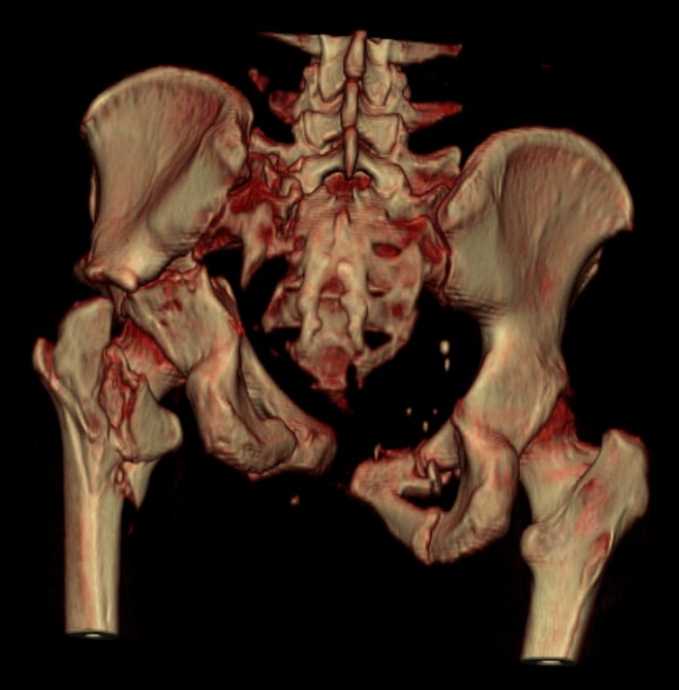

Больная 43 года (промышленный альпинист), 28.07.08 в результате падения с 5 этажа получила политравму: Перелом свода и основания черепа. Вертикально-нестабильное повреждение таза, осложнённое разрывом мочевого пузыря. Чрезвертельный перелом левого бедра. Перелом правой таранной кости, переломовывих правой кубовидной кости. Тупая травма живота, разрыв печени, ушиб почек. Забрюшинная гематома. В день травмы - лапаротомия, ушивание ран печени. Разрыв мочевого пузыря не диагностирован. Течение болезни осложнилось развитием мочевого затёка и обширной пред- и забрюшинной флегмоны, сформировался свищ мочевого пузыря. 19.8.2008 вскрытие, дренировние флегмоны, ревизия мочевого пузыря, обтурация мочевого свища (свищ закрылся в октябре), 1.10.2008 некрэктомия, пластика по Шеде-Лидскому правой кубовидной кости. По результатам КТ диагностирован рак правой почки (диагностическая находка), 8.10.2008 нефрэктомия справа. Переломы велись консервативно. Имеется вертикальное смещение левой половины таза с выраженным отведением крыла (клинически подвижности нет), несросшийся низкий двухколонный перелом левой вертлужной впадины с потерей конгруэнтности, укорочение около5 см, застарелый разрыв лонного сочленения, неправильно сросшиеся переломы обеих ветвей правой лонной кости с укорочением, патологическая подвижность лоно-седалищного фрагмента слева. Правая нижняя конечность неопорна, несмотря на то, что лежа прямую ногу поднимает, ходит на левой ноге (ортопедическая обувь) с костылями, справа тазобедренный ортез. Седалищные нервы работают.Урологи отпустили больную на 6 мес.

с большей вероятностью пациентка придет к эндопротезированию тазобедренного сустава, поэтому необходимо создать надежную "опору" сзади и подготовить бедро к имплантации любой классической ножки.ИМО бедренной кости GN, АНФ на таз,по необходимости остеотомия крестца, восстановление конфигурации задних отделов и устранение вертикального смещения половины таза. дождаться сращения крестца и бедренной кости. второй этап эндопротезирование: ножка цвай-мюллер или спаторно,ацетабулярно онкологическое антипротрузионное кольцо левое либо ацетабулярный компонент по индивидуальным параметрам для протезирования после резекции лонной седалищной костей и вертлужной впадины при онкопатологии. в кольцо пару трения металл\металл с цементной чашкой IMPLANTCAST, т.к. пациентка молодая.лонные кости можно оставить в покое, какой никакой рубец есть. с уважением Сергей.